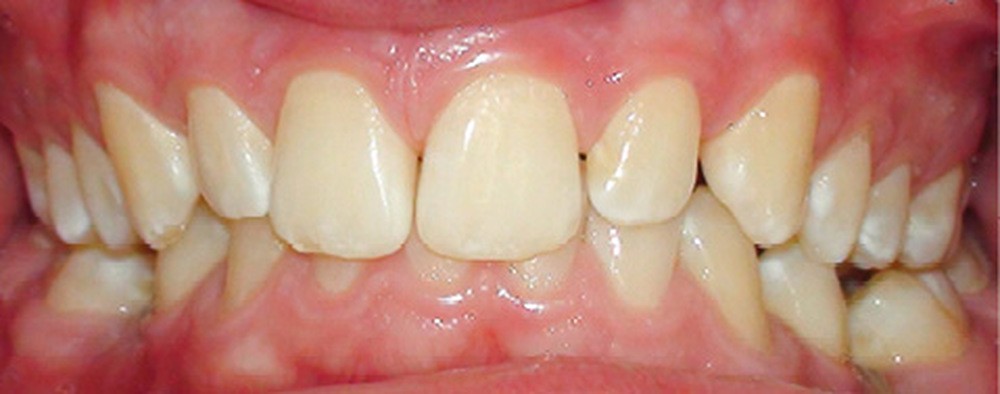

Quand un traitement orthodontique est indiqué dans le cadre de la persistance d’une molaire temporaire, l’orthodontiste doit toujours choisir entre deux solutions : maintenir ou fermer l’espace d’agénésie. Malheureusement, il est parfois confronté à une indication de maintien de l’espace d’agénésie, alors que la dent temporaire ne peut pas être maintenue jusqu’à la fin de la croissance (pour cause de caries, de réinclusion sévère, de perte, etc.) (fig. 1). La pose d’un mainteneur d’espace en fin de traitement est nécessaire, mais rien ne maintient l’os jusqu’à la fin de la croissance et la pose implantaire ! Les patients se retrouvent alors obligés de recourir à des préparations osseuses préimplantaires parfois lourdes. Le but de cet article est de proposer des solutions de maintien du volume osseux après avulsion de la deuxième molaire temporaire.

L’infraclusion de la molaire temporaire, et dans son cas extrême sa réinclusion, est le résultat d’une ankylose de la dent. Cette dent ne pourra plus suivre la croissance de l’os maxillaire ou mandibulaire et ainsi le plan d’occlusion. La molaire temporaire ne présentant pas de germe définitif sous-jacent, elle s’ankylose fréquemment à un stade plus ou moins avancé de l’individu et de la croissance des maxillaires.